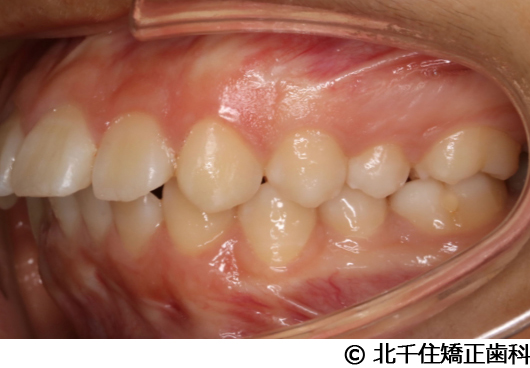

【症例3】叢生

- 治療前

- 治療後

主訴:デコボコ、口元の突出

上下顎第一小臼歯4本を抜歯してワイヤー矯正(セラミックブラケット)。

叢生に対し抜歯を併用した矯正治療により、歯列および咬合関係の調整を行った症例である。治療後は保定装置を使用し、歯列および咬合の安定維持を目的として定期的な経過観察を行っている。